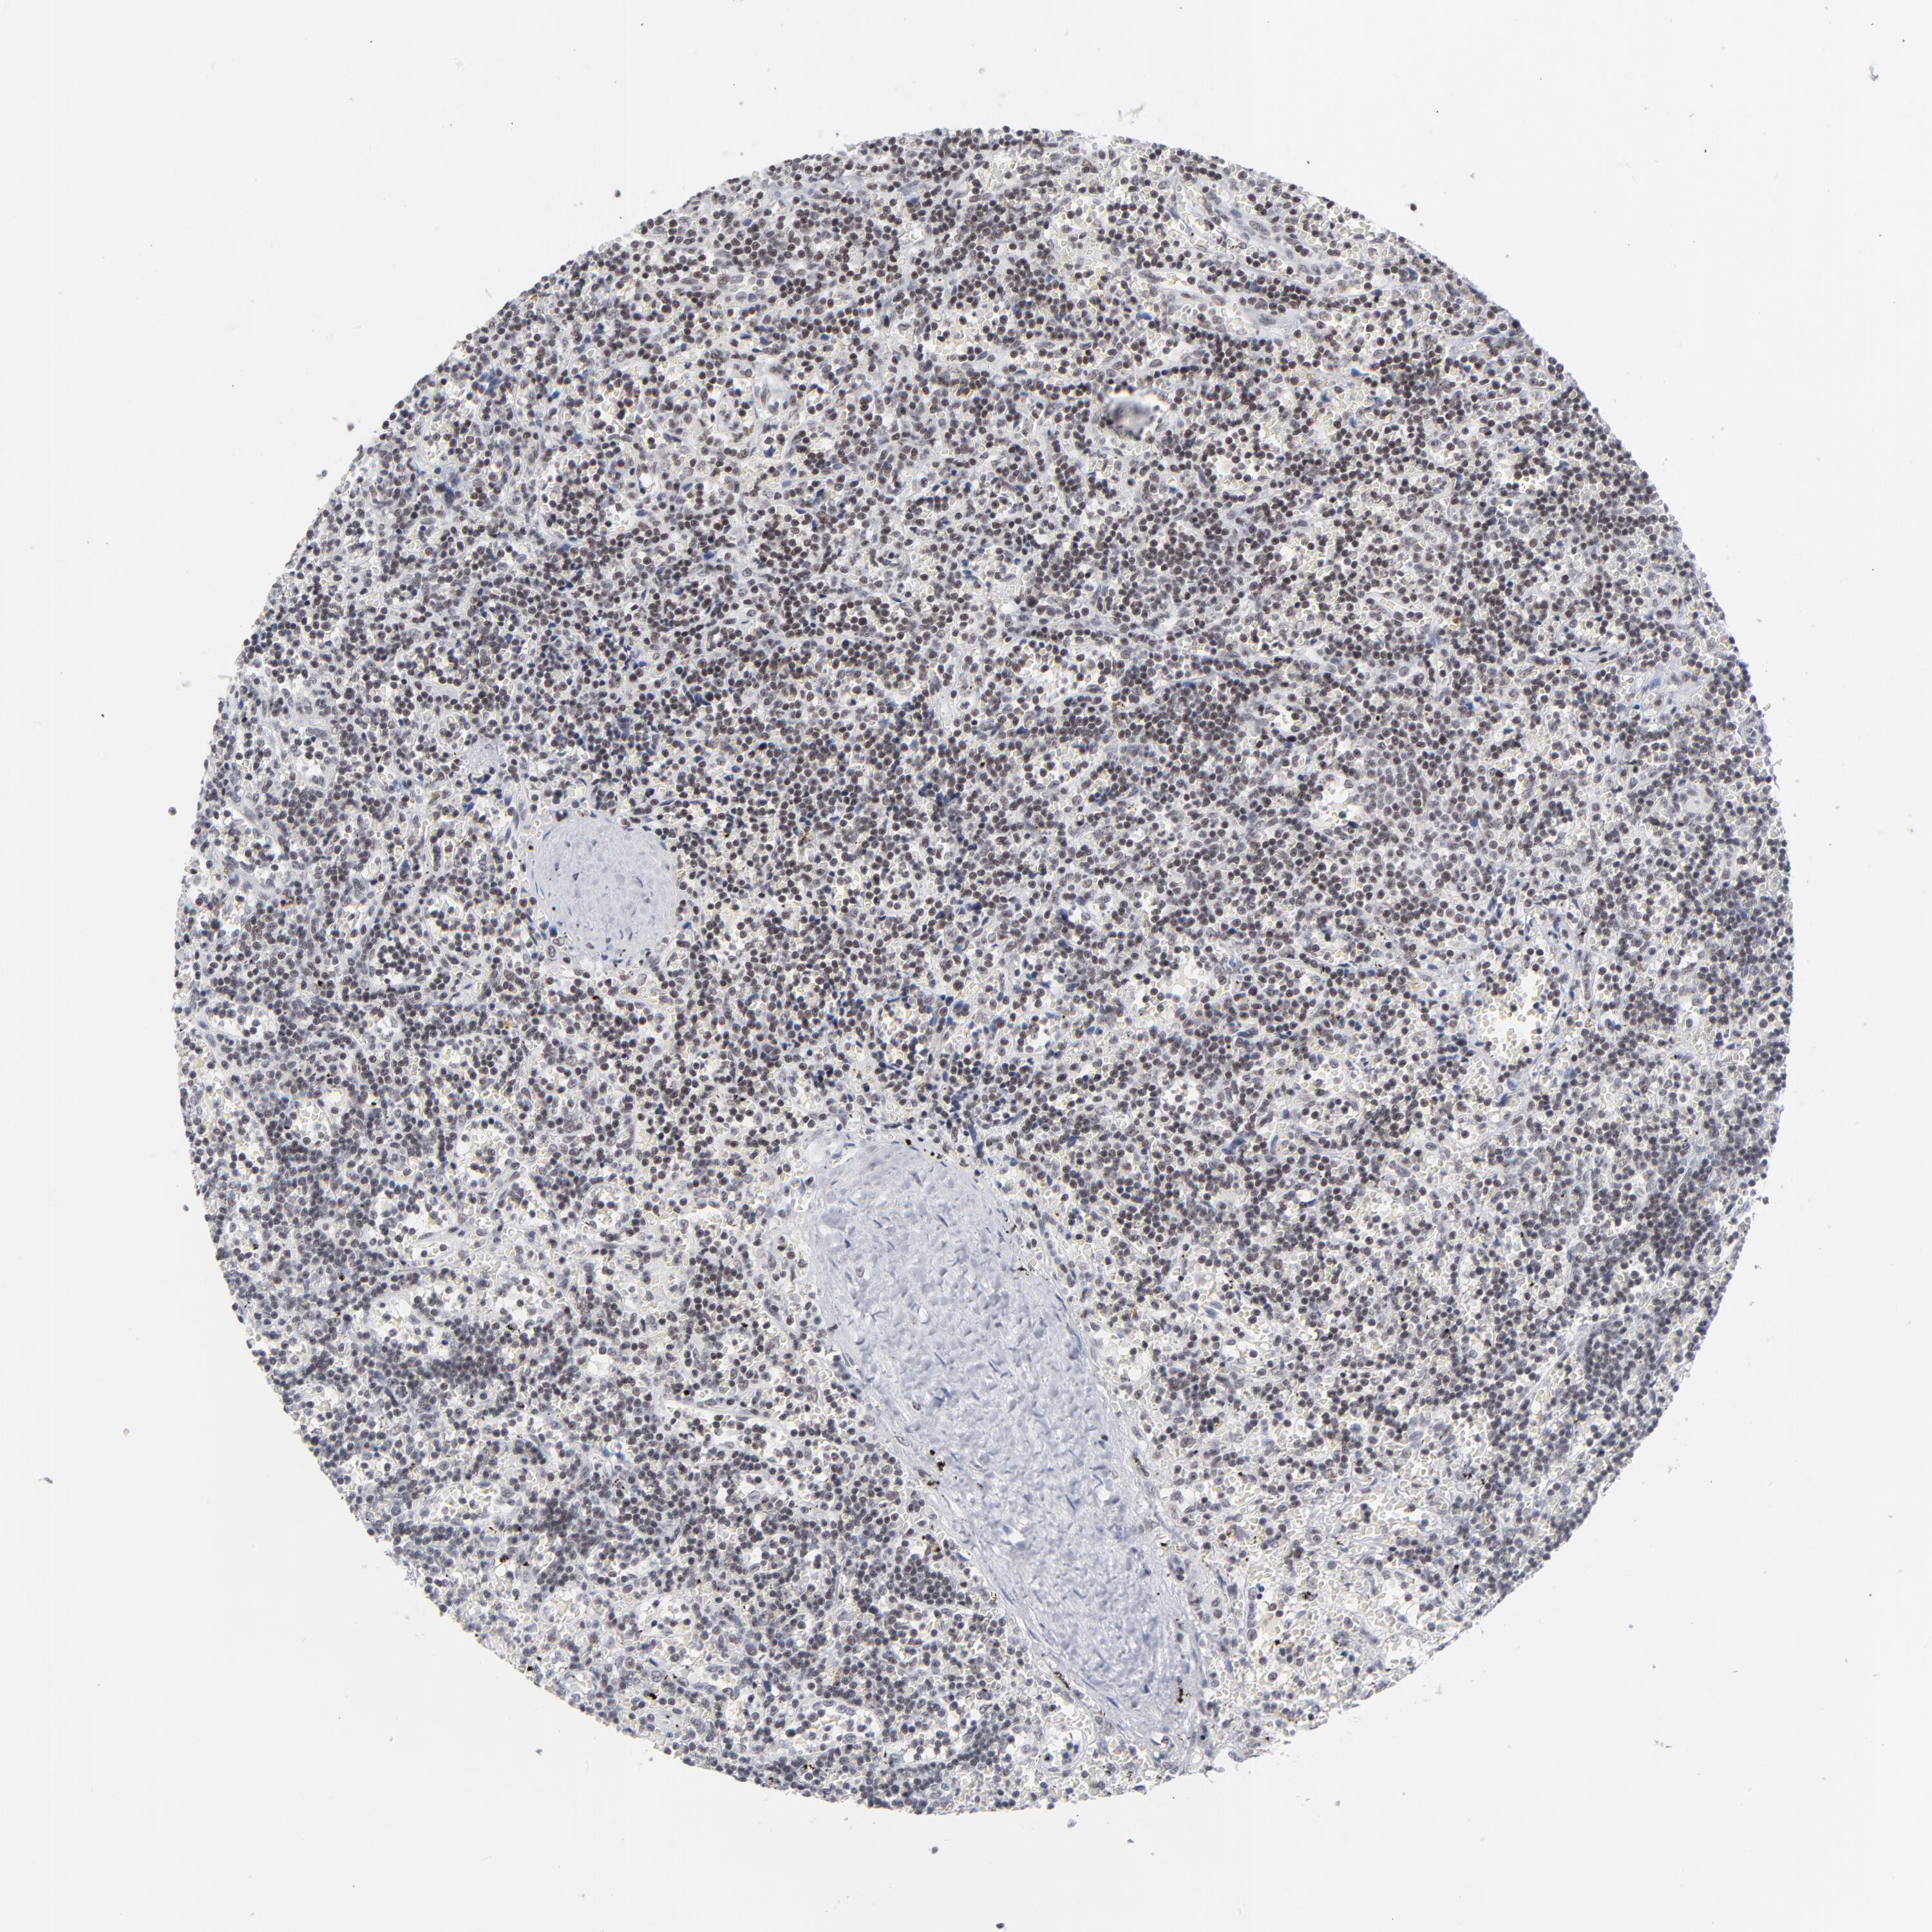

CANCER LYMPHOMA Show tissue menu

LYMPHOMA - Protein expressioni

A mouse-over function shows sample information and annotation data. Click on an image to view it in a full screen mode. Samples can be filtered based on level of antibody staining by selecting one or several of the following categories: high, medium, low and not detected. The assay and annotation is described here.

Each image is clickable and will lead to virtual microscopy that enables deeper exploration of all samples and also displays staining intensity scores, fraction scores and subcellular localization as well as patient and tissue information for each sample.

Antibody HPA003263

Staining

High

Medium

Low

Not detected

Intensity

Strong

Moderate

Weak

Negative

Quantity

>75%

75%-25%

<25%

None

Location

Nuclear

Cytoplasmic/membranous

Cytoplasmic/membranous,nuclear

Malignant lymphoma, non-Hodgkin's type, High grade